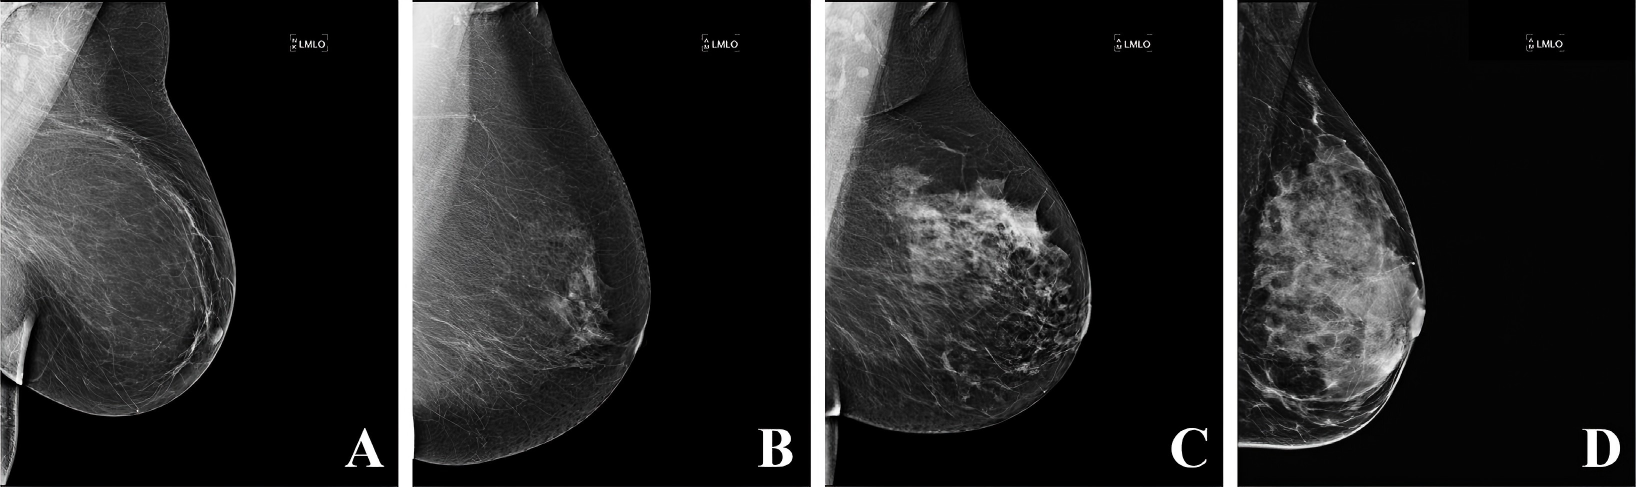

Exploring the Potential of Machine Learning and Deep Learning for Predictive Breast Cancer Analytics

Breast cancer remains a significant global health challenge affecting millions of people worldwide. Early detection is crucial for improving treatment outcomes and survival rates. With the rapid advancement of technology, artificial intelligence (AI) has emerged as a transformative tool in medical diagnostics, particularly in breast cancer detection. This review examines how state-of-the-art machine learning (ML) and deep learning (DL) methodologies have revolutionized breast cancer diagnostics. Techniques such as convolutional neural network (CNN), ensemble learning, transfer learning, explainable AI, and federated learning (FL) have been analyzed for their contributions to addressing multi... More >